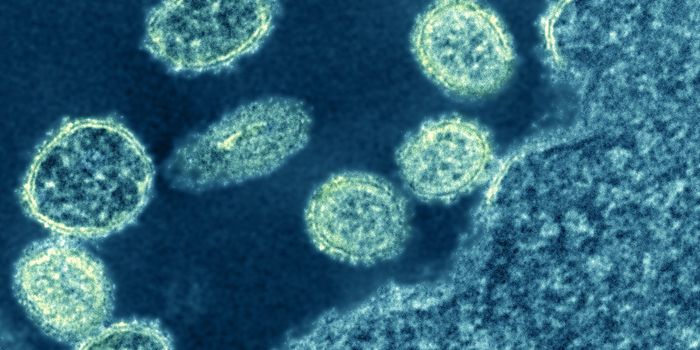

NOV 11, 2021MicrobiologyWhile many people are most familiar with the coronavirus that causes COVID-19, which is called SARS-CoV-2, there are man ...